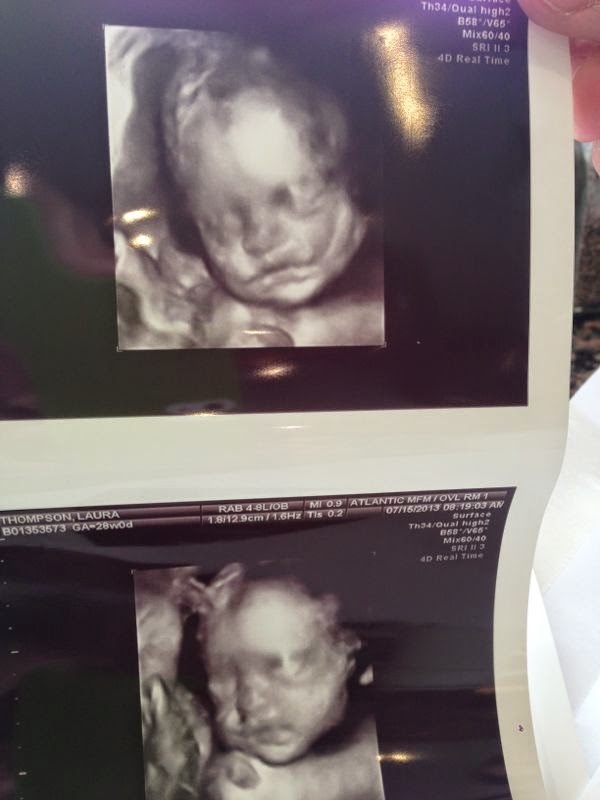

All day at work, I had these painful little cramps around my rib cage and then under my belly button and I just knew...I was growing! Aaaah, such a strange feeling. On the bright side, the larger le bebe becomes, the less crazy I feel for talking to her so much and petting her butt and feet when they come lunging out at me. She's practically a full grown person now!

-Constant dancing in my belly from le bebe. She is ACTIVE with a capital A. None of it bothers me because it's all pretty smooth movements, but the bigger she gets, I imagine this will get a lot more interesting.